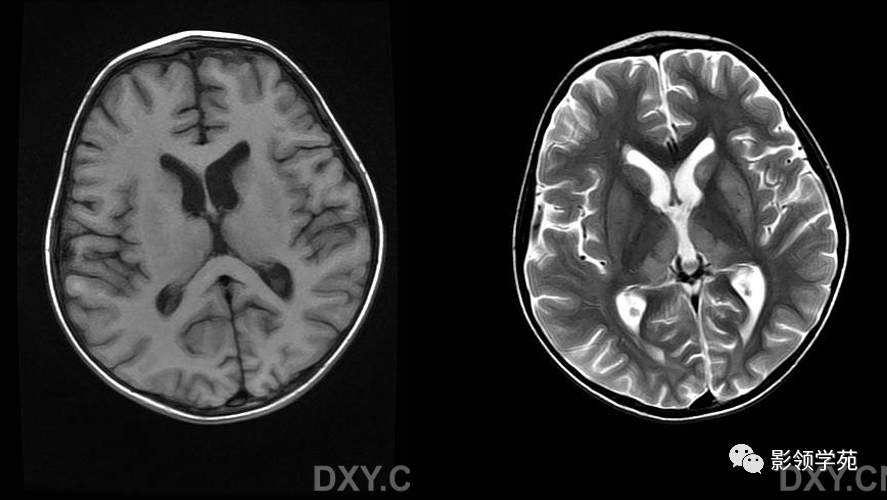

wernicke脑病mri表现

图片尺寸887x500